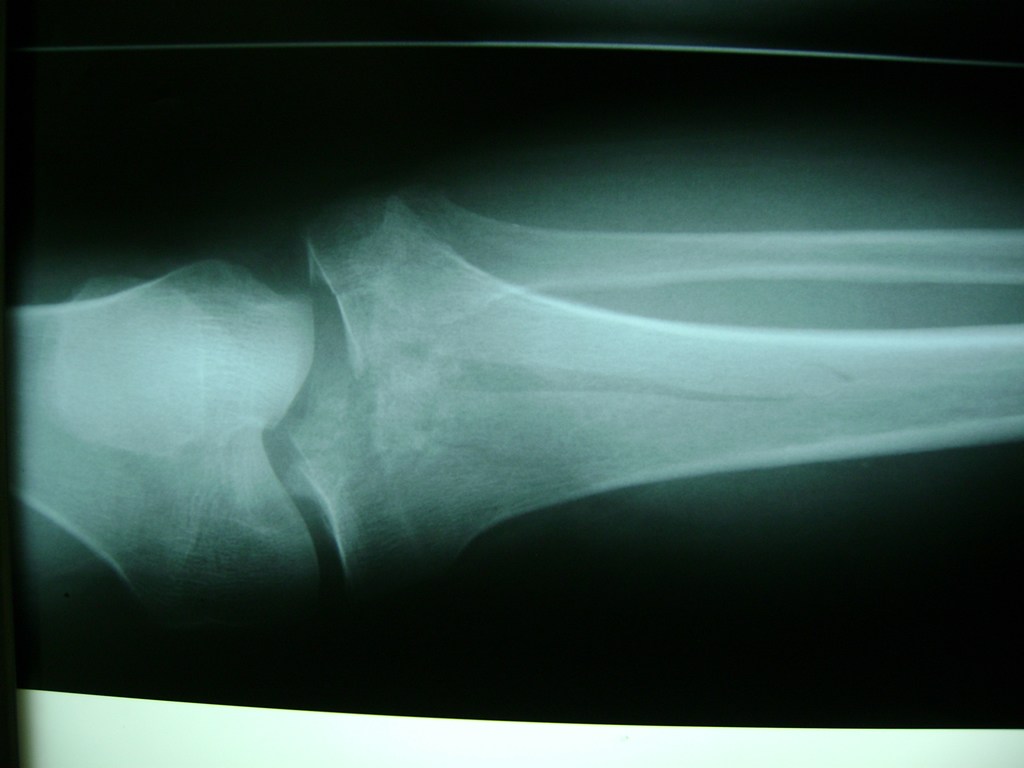

Cirugías de Húmero - Rodilla

La artroscopia de rodilla es un cirugía en el cual la estructura interna de la articulación es examinada ya sea para realizar un diagnostico o para realizar un tratamiento, este procedimiento se realiza utilizando un instrumento parecido a un pequeño tubo llamado artroscopio.